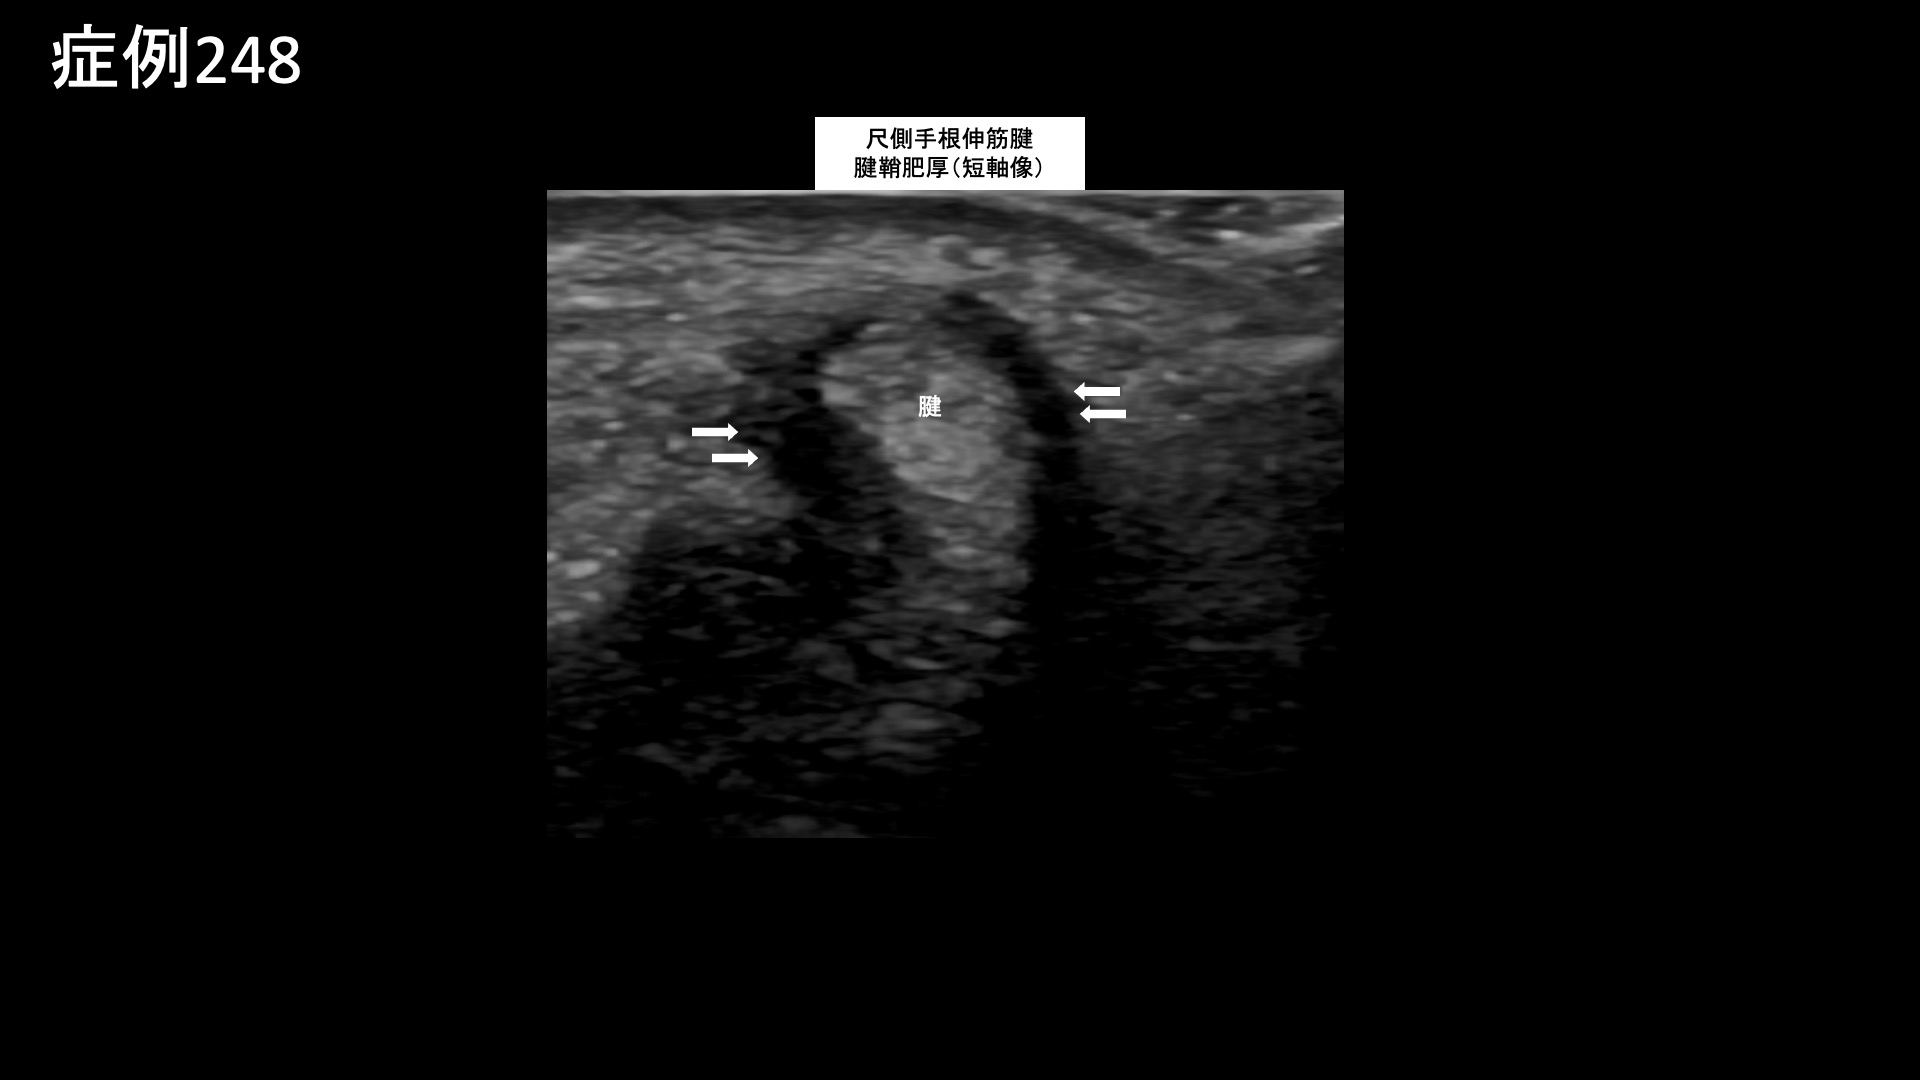

手:ばね指など 【60代:男性】痛くてドアノブも回せない、5年以上続いた手首の痛み。腱鞘炎に変形性手関節症を合併した一例(尺側手根伸筋腱の腱鞘炎、変形性手関節症、ドゥケルバン腱鞘炎) 2025.11.10 鴨井院長による動画解説 受診までの経過 手先をよく使う仕事(巧緻作業)に従事しているほか、趣味で野球やゴルフをされる方です。5年前から右手首が痛むようになりました。使わなければ痛くはならないものの、使うと必ず痛くなりました。ドアノブを回す動作でも痛み、ひどい時は動かせなくなるほどでした。サポーターで固定したりして何とか付き合ってきました。医療機関は度々受診してきましたが、都度レントゲンを撮っても異常は見られず、湿布を処方されるのみでした。この繰り返しで5~6年経過してきましたが、当院の治療を知り受診されました。 診察時の所見 手首の痛みは親指側、小指側とも痛くなるとのことでした。動作確認では、回内回外で特に痛みが誘発されました。背屈はできるものの、一定の可動域制限がありました。エコー検査をすると、尺側手根伸筋腱の腱腫脹および、腱鞘肥厚を認めました。橈側ではより軽度でしたが、一定の腱鞘炎が見られました。更に、手関節橈側において、骨表層不整および低エコー領域を認め、同部位の変形性変化/損傷/変性が示唆されました。レントゲンでは、尺骨に異常は見られなかったものの、手関節の関節裂隙狭小化、および隣接橈骨の骨硬化像を認めました。以上より、尺側手根伸筋腱の腱炎/腱鞘炎、ドゥケルバン腱鞘炎、手関節における変形性関節症と診断しました。治療適応と判断し、モヤモヤ血管(病的新生血管)に対する運動器カテーテル治療(微細動脈塞栓術)を受けていただきました。 治療の所見 血管造影を行うと、尺骨動脈で尺側手根伸筋腱および手関節に一致して、モヤモヤ血管が濃染像として描出されました。骨間動脈でも手関節周囲に、同様にモヤモヤ血管を認めました。治療後は画像上速やかに消失しました。橈骨動脈の治療も行い終了しました。 治療後の経過 治療後2週間ではまだ大きな変化はありませんでしたが、治療後2ヶ月の再診時には大幅に改善し、元の痛みの1/10程度となっていました。しばらく止めていたゴルフもしたいくらいと言われました。その後も再発することなく順調に経過し、治療後6ヶ月時点では、普段の痛みはゼロ、無理をすると痛むことはあるがそれでも当初の1/10とのことでした。腱鞘炎のみではなく、手首の変形性関節症も伴っているため、使い過ぎにはくれぐれも注意していただくようお話しし、終診としています。 腱鞘炎の詳細はこちら 【50代:女性】長い距離を歩くと痛くなる、登山家に生じた両膝の痛みに対するモヤモヤ血管治療(膝蓋下脂肪体炎、腸脛靭帯炎) 前の記事 【50代:女性】ステロイド軟膏塗布が原因で3年以上続いた顔面酒さに対するモヤモヤ血管治療(顔面酒さ、ステロイド性皮膚炎) 次の記事